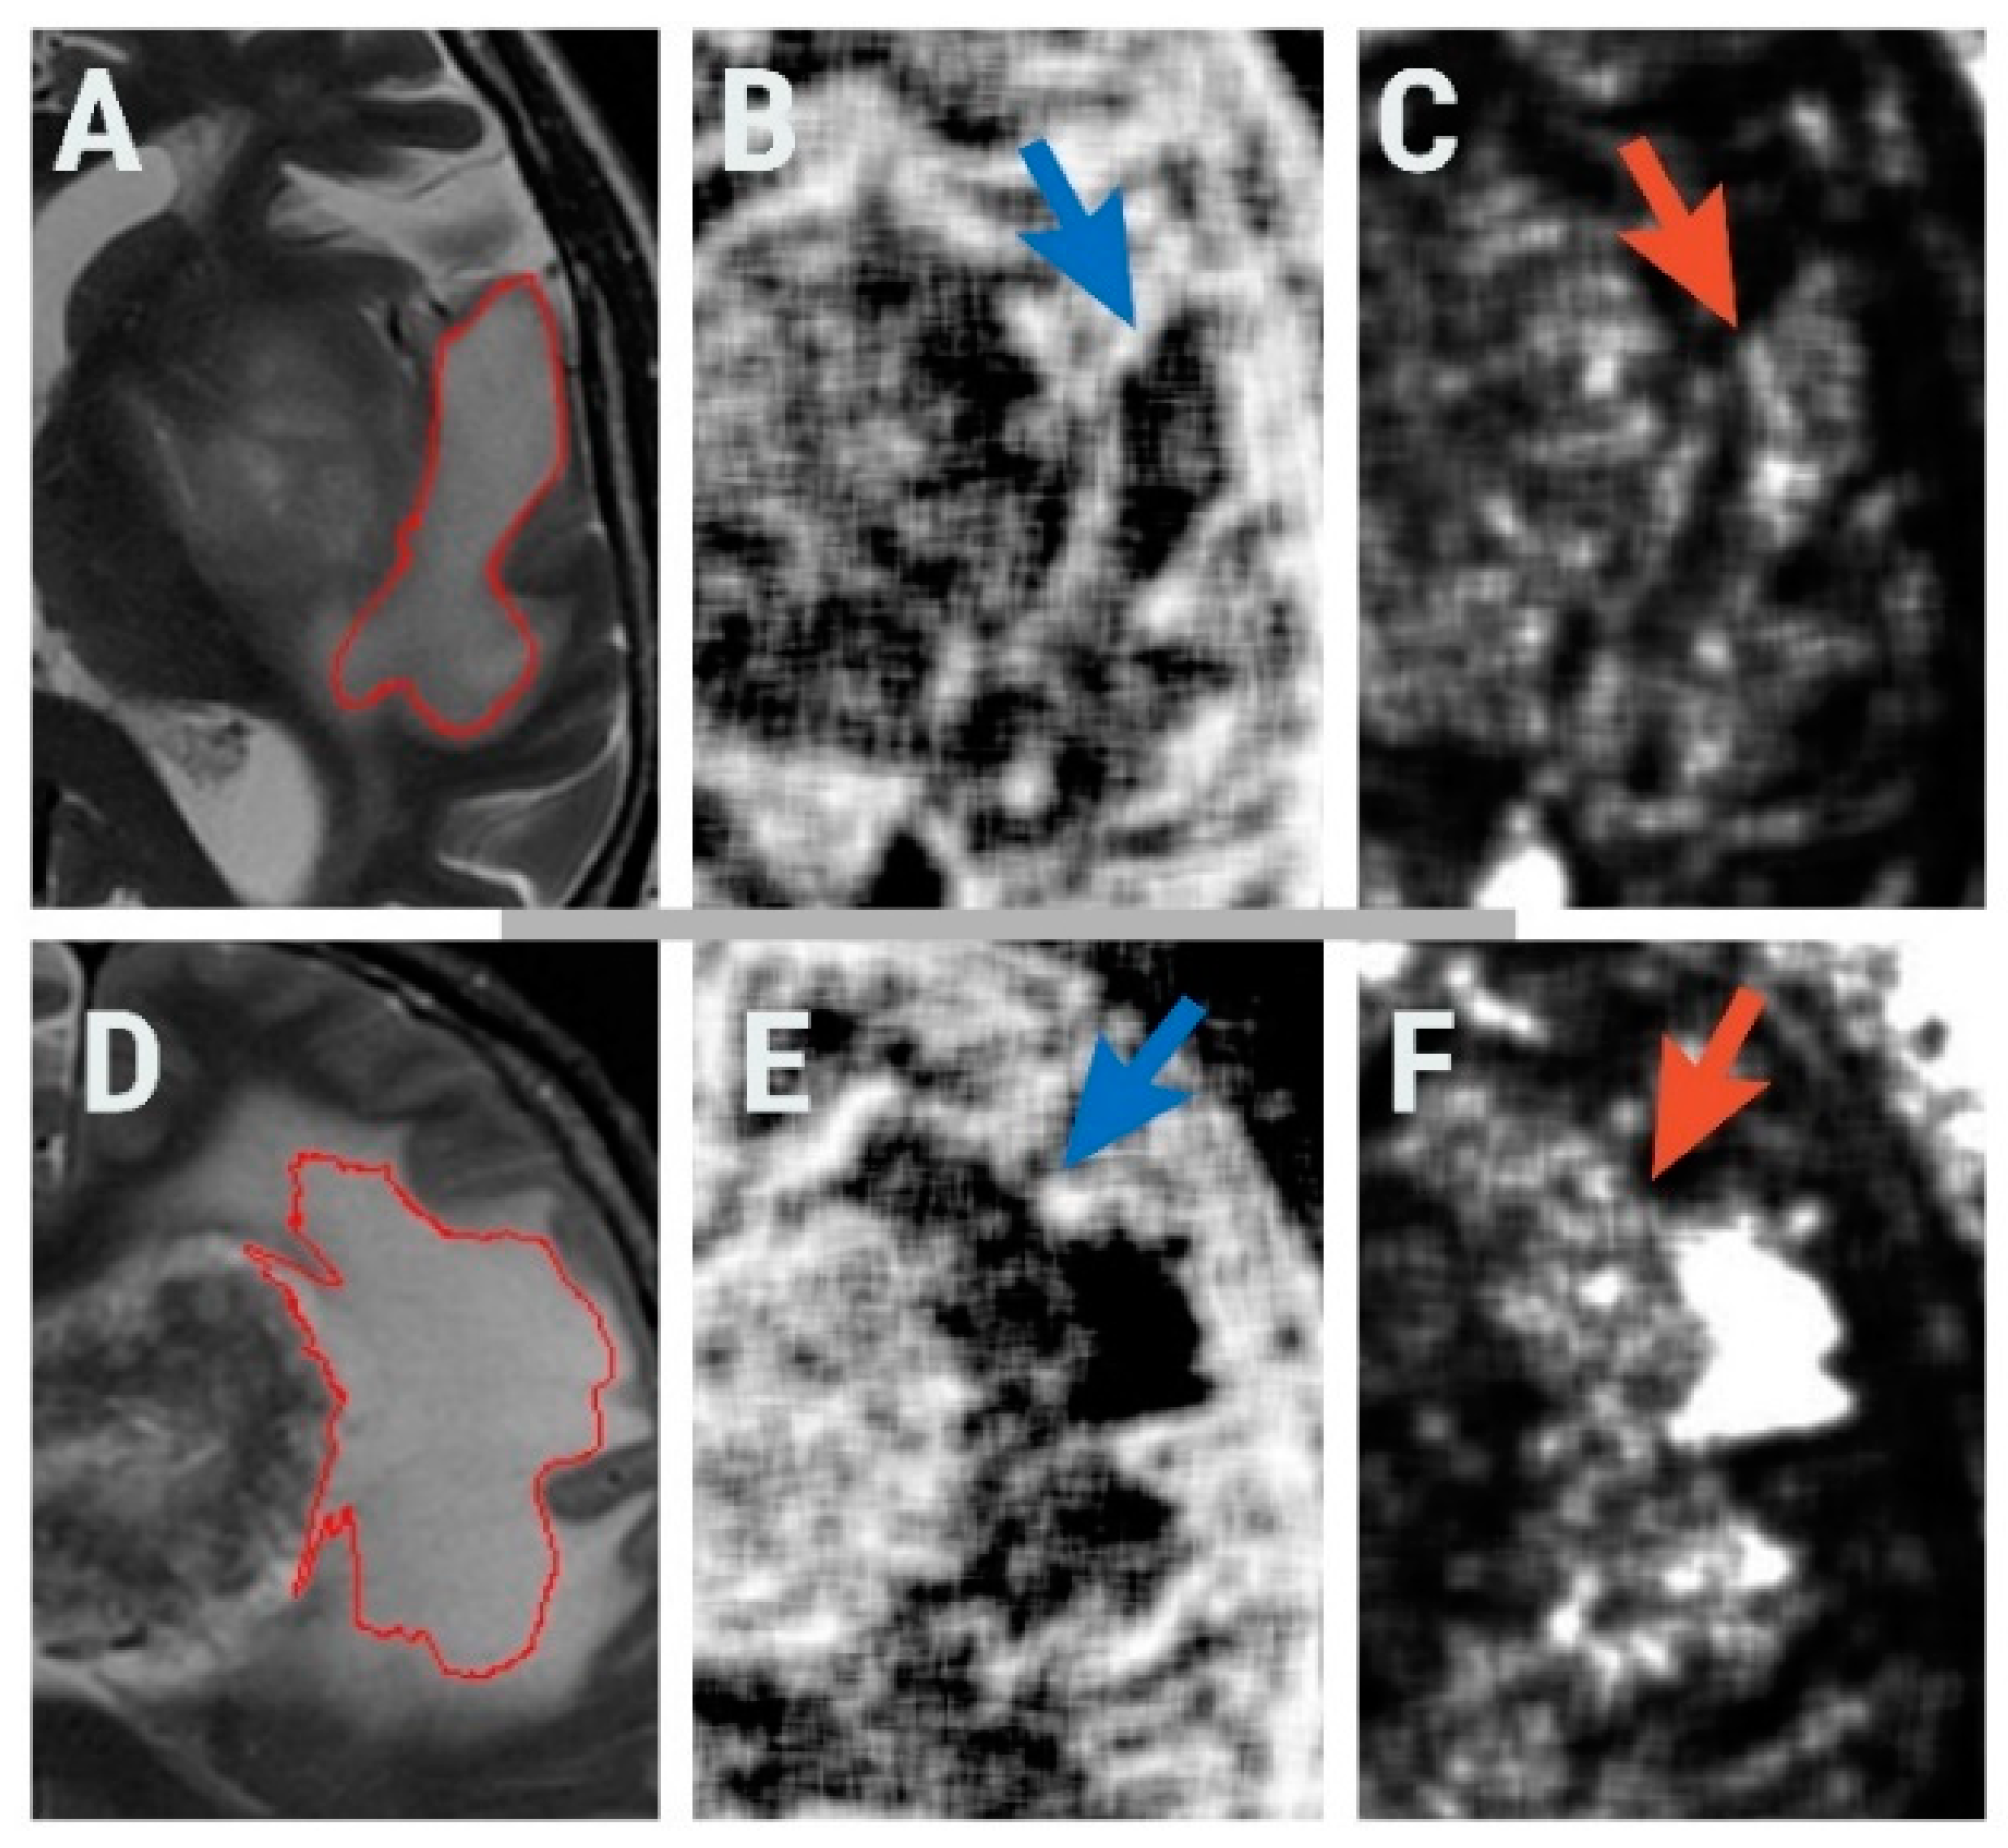

2.3. Texture Analysis Protocol